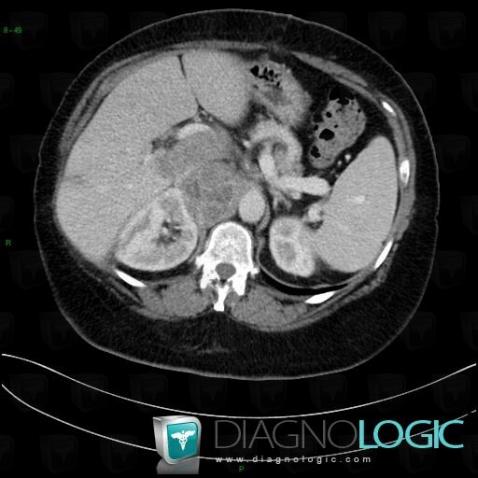

Adrenocortical carcinoma, Retroperitoneum, CT

Here is the specific information in the key image above:

- Diagnosis Adrenocortical carcinoma, Location(s) Retroperitoneum, with gamuts Low density retroperitoneal mass